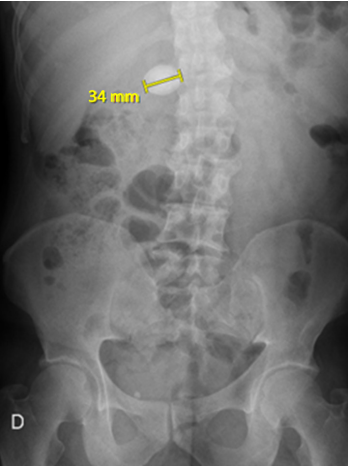

Laboratory tests showed electrolyte imbalance in 14 patients (87.5%) and liver function tests abnormalities in five patients (31.2%). A correct preoperative diagnosis of GI was reached in 13 patients (81.2%); the remaining was diagnosed during surgery. The classical image signs of GI were visualized in 7 patients (43.7%) on plain abdominal radiograph (Figure 1), in six patients (37.5%) on ultrasound (Figure 2) (Figure 3), and in 13 patients (81.2%) on CT (Figure 4) (Figures 5a & b).

Figure 4 Computed tomography depicts an endoluminal oval-shaped image with calcium density, consistent with a migrated gallstone within the terminal ileum.

Figure 6 Computed tomography reveals a calcium density endoluminal foreign body of 34 mm, located in the topography of the duodenum.